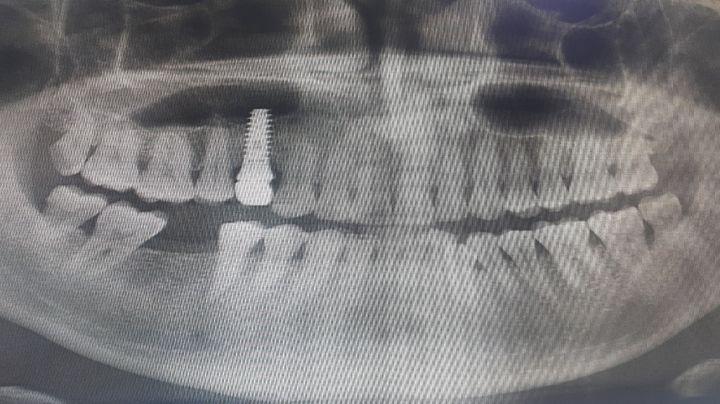

치협은 치과 의료행위 특수성을 무시한 '수면' 마케팅'을 해서는 안된다고 했다. 특히, 치과 임플란트 시술은 일반적인 내시경 검사와 달리 ▲상대적으로 시술 시간이 길고 ▲환자의 협조(고개 돌리기 등)가 수시로 필요하며 ▲구강 내 시술 특성상 혈액, 타액, 기구 등이 기도나 폐로 흡인될 위험이 상존한다.

치협은 최근 강남 소재 치과에서 의학하진정법으로 임플란트 시술을 받다가 사망한 사고를 계기로 의식하진정법의 적응증 엄격 준수, 실시간 환자 모니터링 체계, 응급 대응 시스템 등 내부 가이드라인을 재점검할 방침이다. 또한 관계 기관과 협력해 과장된 의료광고와 불법적인 환자 유인 행위에 대해 단호히 대처할 예정이다.